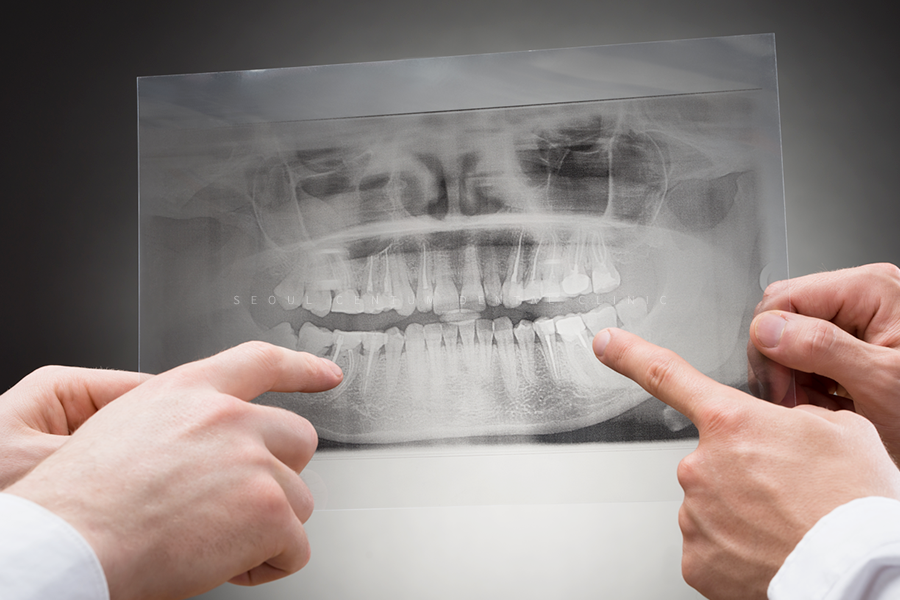

어버트먼트와 크라운 제작이 완료되면

수복해서 파노라마를 찍고 마무리합니다.